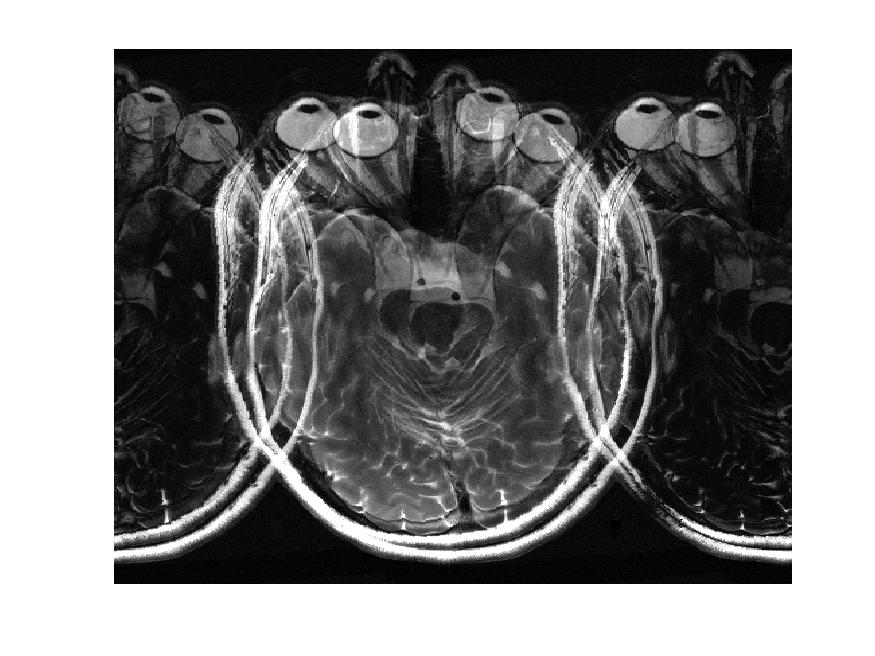

SISMIK le modèle de correction

Nous proposons un système de correction de mouvement rétrospectif sur les données de mesure IRM (espace-K) appelé SISMIK qui reconstruit des images avec moins d’artéfacts de mouvements.

Le système est dit hybride entre l’intelligence artificielle et les méthode algorithmiques plus traditionnelles, combinant les avantages des deux approches.

1. Les mesures “brutes” sont montrées à un réseau de neurones convolutionnel (CNN) entraîné au préalable.

2. le CNN estime pour chaque ligne d’aquisition le déplacement relatif effectué par rapport au lignes adjacentes.

3. le réseau produit une trajectoire complètes (mouvement dans le temps) le long de l’acquisition

4. la trajectoire et les données brutes sont envoyées au second algorithme afin qu’il corrige et reconstruise les images correspondantes.

L’IRM, technique d’imagerie médicale non invasive, est très sensible aux mouvements du patient car l’acquisition spatiale se fait de manière ségmentée. L’information complète requiert une séquence longue. En effet, l’IRM ne fait pas directement une image comme en rayon-X (RX ou CT-scan). En IRM, Le signal de résonance magnétique mesuré est enregistrée dans l’espace des fréquences spatiales appelé “espace-K”. L’image finale utilisée par les radiologue est obtenue par “reconstruction” via une transformation mathématique, la transformée de Fourier.